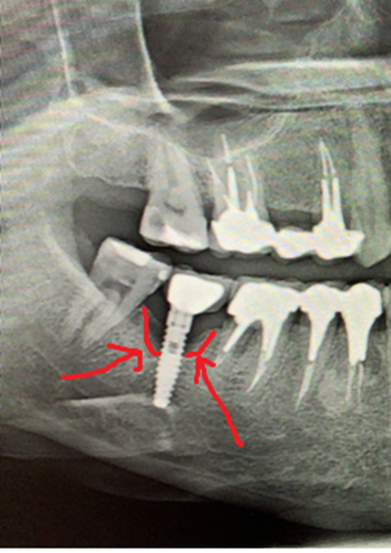

Январь 2023. Произошел спор с пациентом, который 4 месяца назад удалил зубы в городской поликлинике, где ему разворошили всю кость и он был очень удивлен, почему мы не сможем сходу установить импланты без наращивания. Этой ситуацией хотелось с кем-то поделиться, причем с тем, для кого это не рутина. Я вспомнил про свои посты. И меня понесло. Начал писать статьи одну за другой. И в какой-то момент я заметил, что чем больше я пишу, тем больше народ начинает задумываться о своем здоровье. Люди стали засыпать меня вопросами, я по мере возможности отвечал, иногда совсем поражался тем, насколько люди у нас не просвещены в этом плане. Стало поступать множество призывов помочь, просили персональной консультации.

Кидаем снимки, если есть.

Если есть КТ, то кидаем на почту vadbel1310kt@yandex.ru В теме письма указываем ваш никнейм телеграме, чтобы я мог понять кто это прислал, посмотреть и ответить.